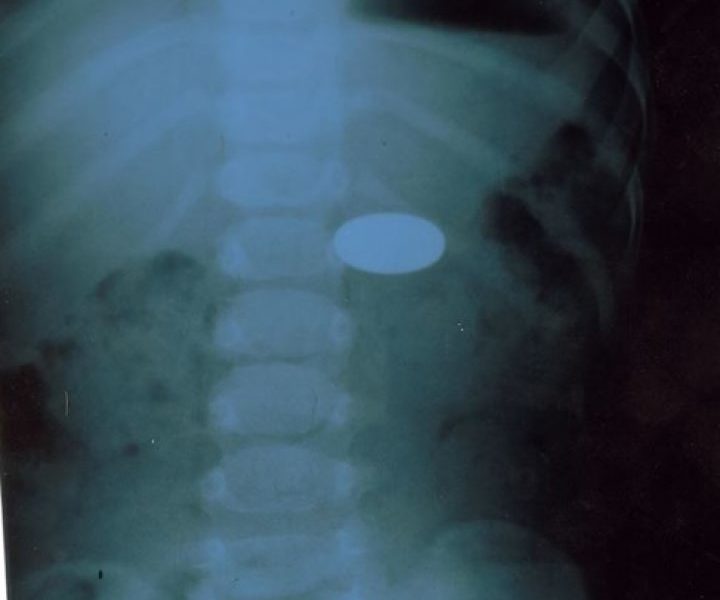

O copilă de 2 ani şi 6 luni a ajuns la spital după ce a înghiţit o monedă de un leu. Fetiţa a fost transportata la Institutul Mamei şi Copilului, unde medicii din candrul secţiei Endoscopie.

Victor Rașcov (medic endoscopist), Semeniuc Alexandra (asistentă medicală), Glijinschi Anastasia (anesteziolog), au conlucrat în procedura de extragere cu succes a monedei din tractul digestiv al fetiţei.

Situaţia nu este fără precedent. Potrivit datelor centrului medical, de la începutul acestui an a fost efectuate deja 16 intervenții de extragere a corpurilor străine din tractul digestiv superior la copii, dintre care în 7 cazuri fiind vorba de înghițirea unor monede.